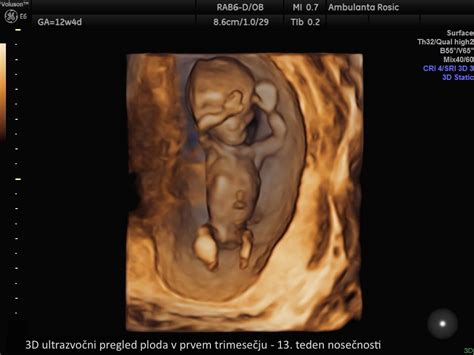

Horionske resice so del razvijajoče se posteljice, ki obdaja plod v zgodnji nosečnosti. Te resice delijo enak genetski zapis kot plod, zato so idealen material za genetske analize. Biopsija horionskih resic se običajno izvaja med 11. in 13. tednom nosečnosti, najpogosteje v 12. tednu. Zdravniki jo priporočajo v naslednjih primerih:

Postopek biopsije horionskih resic je relativno enostaven in poteka pod stalnim ultrazvočnim nadzorom. Zdravnik najprej z ultrazvokom določi lego ploda in posteljice. Nato s tanko iglo, skozi trebušno steno nosečnice, prodre do horionskih resic in odvzame majhen košček tkiva. Ta vzorec se nato pošlje v laboratorij na genetsko analizo. Postopek običajno traja le nekaj minut.